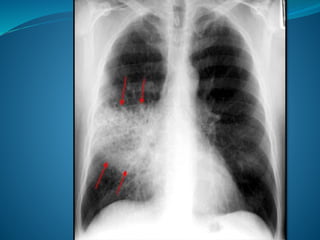

 X-ray chest P/A & Lateral view-consolidation

Pneumonia

INVESTIGATIONS  CBC,ESR-neutrophilic leucocytosis X-ray chest P/A & Lateral view-consolidation  Sputum Gram stain & culture-organism  Blood C/S-organism  ABG (arterial blood gas analysis)